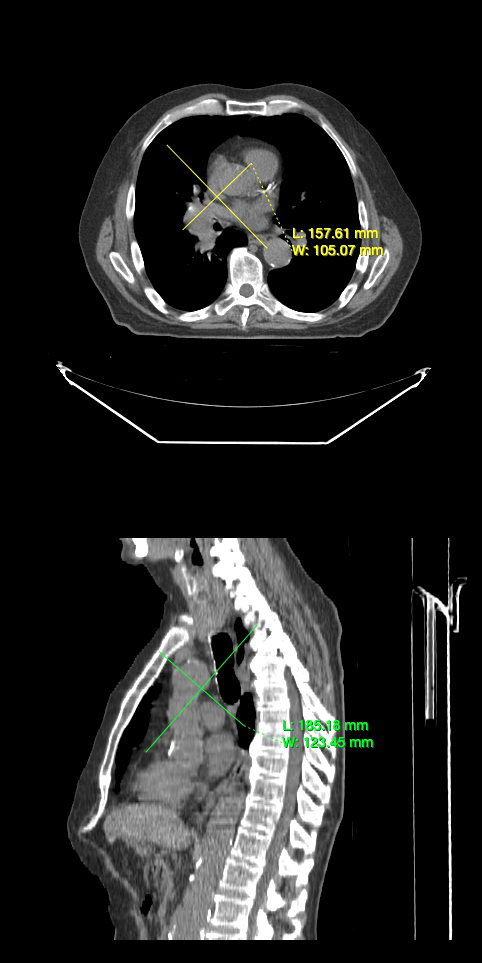

Annotation Tools

In this tutorial, you will learn how to use annotation tools to annotate.

You should be able to annotate images with the tools you added.